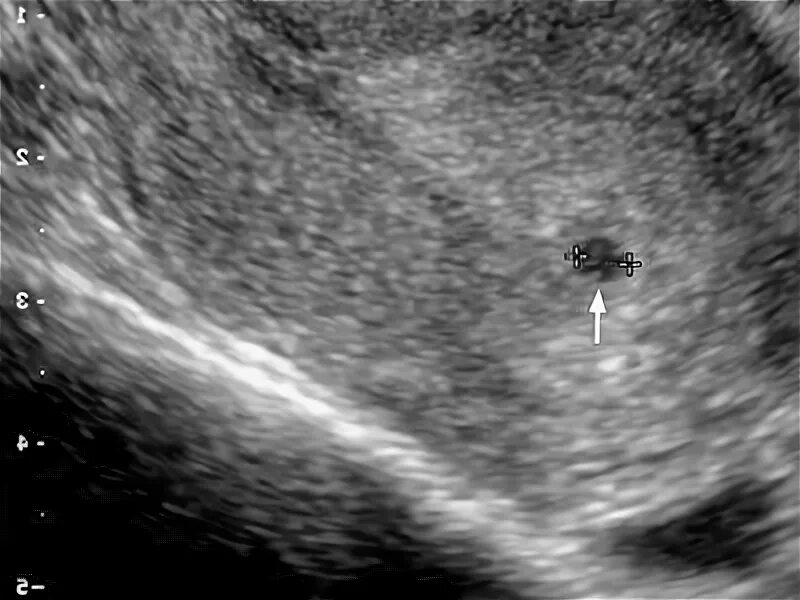

Желточный мешок 2 мм